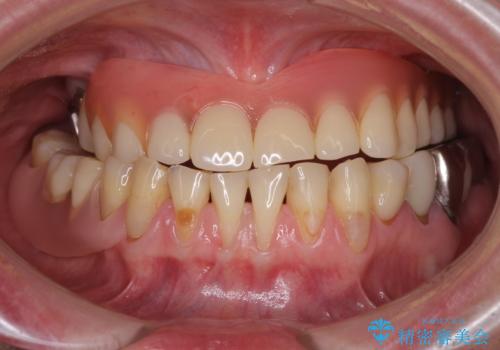

- 咬み合わせにより下の前歯の歯肉が退縮してしまい、根が見えていることが気になるとのことで来院された患者様です。

歯肉退縮に対して、上顎からの結合組織移植術(CTG)により、歯根の被覆を行うとともに、歯肉の厚みを増すことで将来の退縮リスクを抑制することとしました。

歯肉が大変薄かったため、歯肉移植による根面被覆の効果はそれほど高くないように思われましたが、想像以上に歯肉の位置を回復させることができました。

歯肉の厚みも十分に獲得でき、患者様には大変満足していただきました。